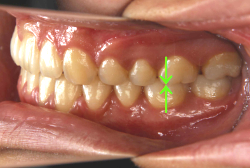

歯科矯正用アンカースクリューを用いた症例(骨格性反対咬合 非抜歯治療)

「ものがうまく噛めない」という主訴で来院したケースです。診断の結果、「骨格性反対咬合に伴う咬合不良+軽度叢生」と判明しました。原因としては特に下顎の左側が過成長したため、骨格性反対咬合になり、特に左側での噛み合わせが非常に悪くなっていると診断しました。初診時の写真を見ると、上下の正中線の大きなズレ、左側の噛み合わせの不良がはっきり分かります(黄色の矢印と緑の矢印は一致しているのが正しい状態です)。